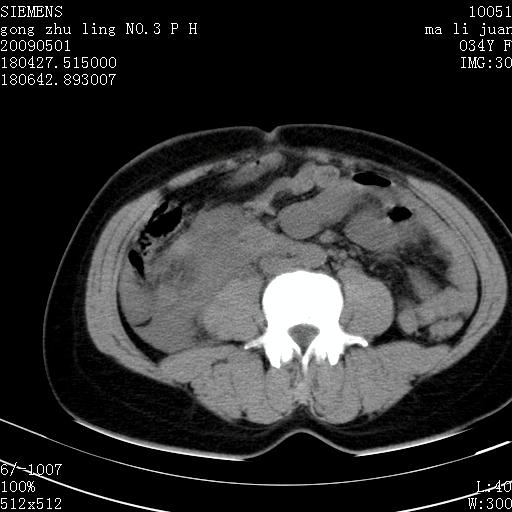

标题: CT19733:右肾碎裂

青年女性,骑摩托车摔伤。

右肾碎裂伤,包膜下血肿。

术中仅见右肾碎裂,肾蒂血管未见断裂。

右肾破裂伴肾包膜下及肾周血肿。

支持 右肾破裂伴肾包膜下及肾周血肿